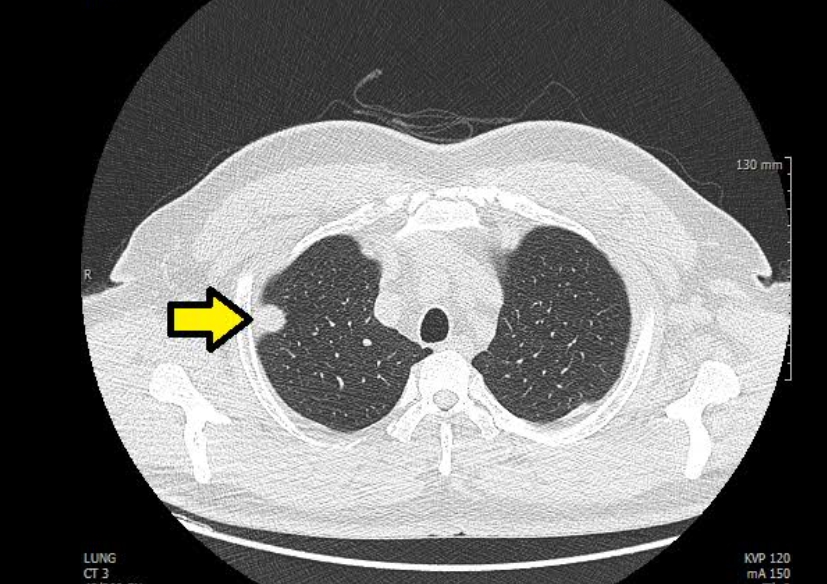

흉부 엑스레이 결절음영

결절음영이란 말은 엑스레이에서 ‘혹처럼 보이는 부분’을 뜻해요. 작게 하얗게 보이는 점, 혹은 둥근 모양의 그림자가 결절음영입니다. 이게 보이면 대부분은 오래된 염증, 흉터, 석회화(염증이 낫고 남은 흔적)일 때가 많아요.

하지만 간혹 크기가 크거나 모양이 울퉁불퉁한 경우엔 폐암 같은 질환을 의심하기도 합니다. 그래서 보통은 “추적 관찰”을 권해요. 6개월 또는 1년 뒤 다시 찍어서 변화가 없는지 보는 거죠. 제 지인 중 한 분도 건강검진에서 결절음영이 나와서 놀랐지만, 재검 때는 흔적만 남고 없어졌어요. 그때 이후로는 주기적으로 검사받는 걸 잊지 않으신다고 하더라구요.

Q3. 흉부 엑스레이에서 결절이 보인다고 하는데, 꼭 암인가요?

A. 대부분의 결절은 암이 아닙니다. 예전 감염의 흔적이나 석회화된 조직이 남은 경우가 훨씬 많아요. 하지만 결절의 크기나 모양, 가장자리 윤곽이 불규칙하다면 악성 가능성도 있으므로 정기적인 추적검사를 권합니다. 요즘은 저선량 CT로 더 정확하게 관찰할 수 있습니다.